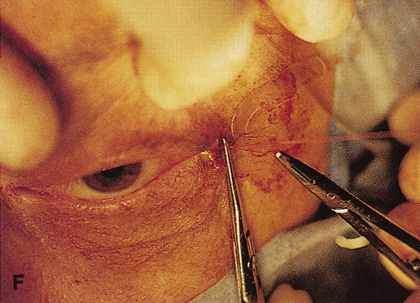

Fig. 6. Lateral orbitotomy through upper eyelid skin crease A. Photo demonstrating right globe ptosis present for more than 2 years. B. Axial CT scan showing a well outlined oval lesion in the lacrimal gland

fossa. C. Coronal CT showing lesion pushing globe inferiorly. D. Skin crease excision marked for lateral orbitotomy. E. Lateral orbital rim exposed. Bone cuts made above frontozygomatic suture

and at zygomatic arch. F. Lateral wall removed. Subperiosteal space exposed. Hard tumor could be

palpated in area of lacrimal gland. G. Benign mixed tumor of lacrimal gland removed. H. Bone sutured into place. I. Skin crease closed. |

along the lateral orbit (see Fig. 6F), and damage to these